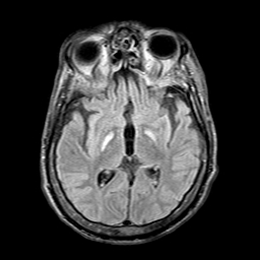

Burke-Fahn-Marsden rating scale26 (BFMRS) score was: 104/120. A T2 weighted brain Magnetic Resonance imaging (MRI) scan showed hypersignal bilaterally involving both pallida, mostly affecting the most medial part (Figure 2). Treatment attempts with Trihexyphenidyl, Carbidopa-Levodopa, Carbamazepine, Clonazepam, Phenytoin and Baclofen were unsuccessful. Botulinum toxin injections provided some relief of the muscular contractions but rapidly became ineffective considering the importance of dystonic movements. The family gave informed consent for DBS surgery. As the main output of the pallidum is the ventrolateral thalamic nuclei (Voa) and the centromedian-parafascicular nucleus,30,34 we decided to target Voa for DBS and hoped it would act directly on the last distal part of the retroactive feedback to the motor cortex from GPi.

Figure 2 Pre-operative MRI showing selective necrosis of the Globus Pallidus interna, predominantly on the right side (above images are in radiological view).